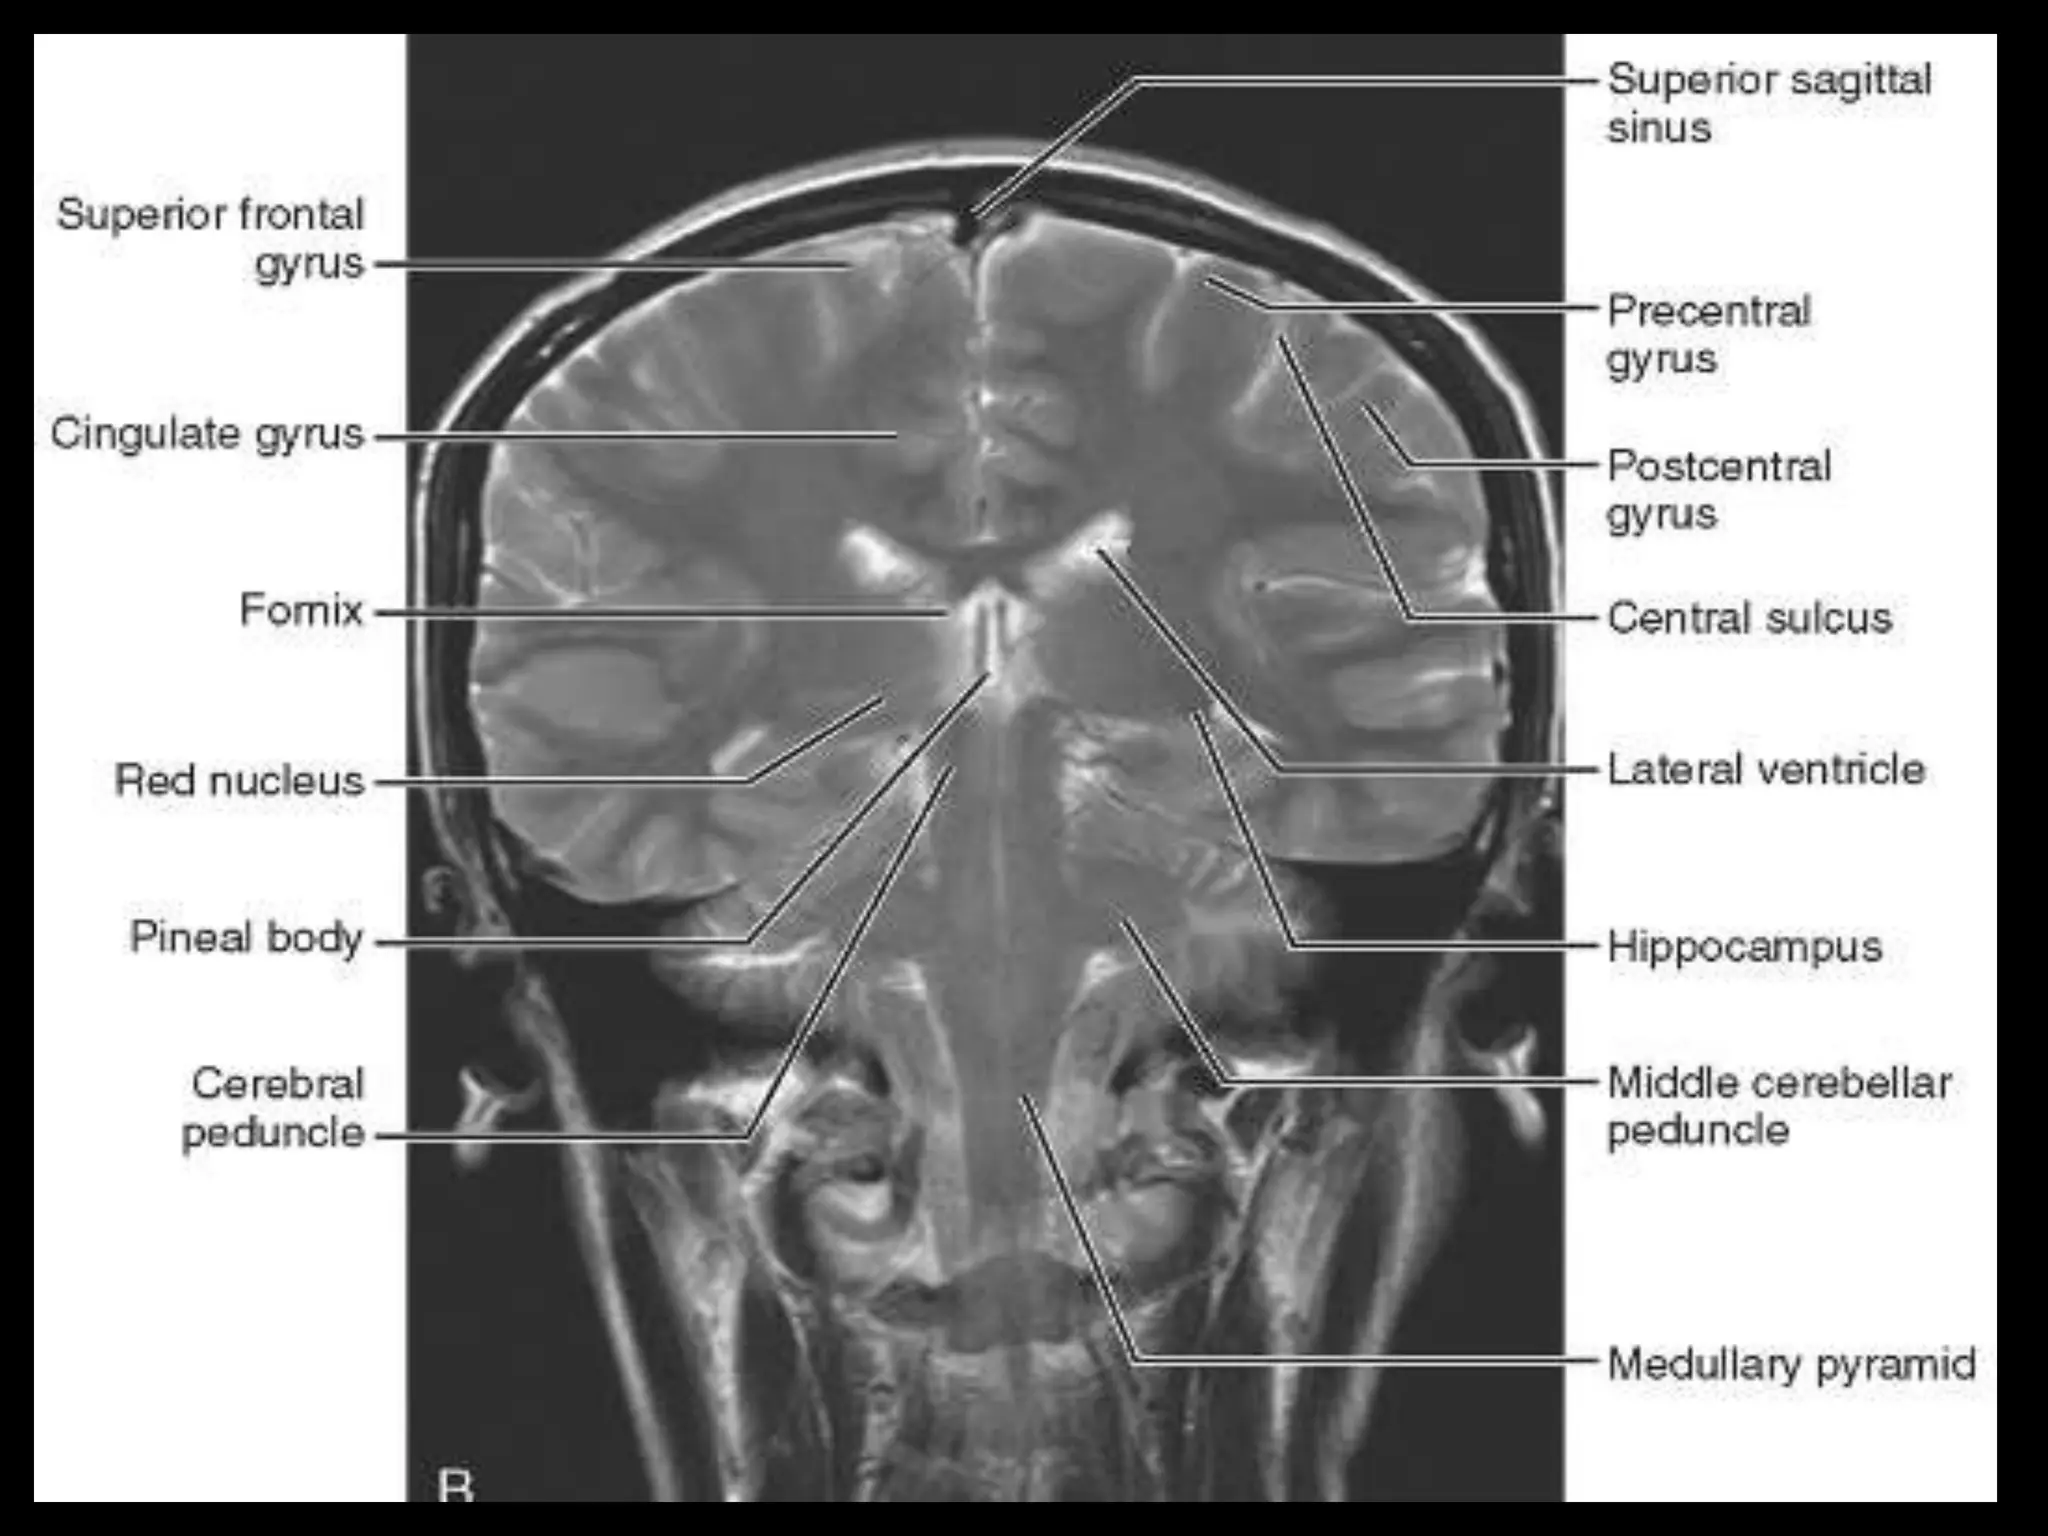

Its hemispheric surface is convoluted and has gyri and sulci. The

brain consists of the cerebrum, cerebellum, and brain stem.

The two cerebral hemispheres are separated by

interhemispheric fissures and falx cerebri. On the lateral surface of the

brain, the sylvian fissure (lateral fissure) and the rolandic fissure (central

fissure) separate the cerebral hemisphere into the frontal lobe, temporal

lobe, parietal lobe, and a line drawn from the parieto-occipital sulcus

onto the preoccipital notch, delineating the boundaries of the parietal

and temporal lobes from that of the occipital lobe.

The frontal lobe, the largest of all the brain, has four principal

gyri: the precentral gyrus and the superior frontal, middle frontal, and

inferior frontal gyri. The precentral gyrus, parallel to the central sulcus,

together with the anterior bank of the central sulcus, comprises the

primary motor area, which is one of the most important cortical areas

for movement. Rostral to the precentral sulcus is the premotor area,

another important area for movement. The middle frontal gyrus contains

Brodmann’s area 8, known as the frontal eye field, which is important for

conjugate eye movements. Another important motor area for speech

called Broca’s area, is located at the triangular and the opercular parts of

the inferior frontal gyrus in the dominant hemisphere.

In the parietal lobe, there are a postcentral gyrus, a superior

parietal lobule, and an inferior parietal lobule. The postcentral gyrus

is a primary somesthetic area involved in general body sensation.

In the temporal lobe, the superior, middle, and inferior temporal

gyri are separated by the two transverse sulci. The posterior fossa

contains the cerebellum and brain stem.